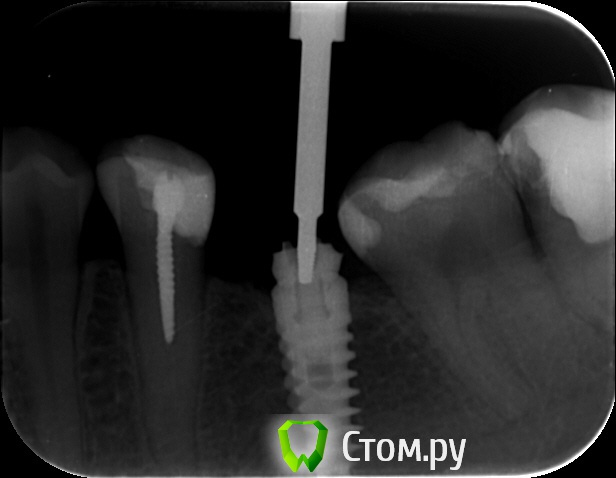

an_ver Опубликовано 29 мая, 2014 Поделиться Опубликовано 29 мая, 2014 Кто то пытался достать))) Абатмент спили в ноль...головку винта своротили.Набор Нео 3 Ссылка на комментарий

molchanoff Опубликовано 29 мая, 2014 Поделиться Опубликовано 29 мая, 2014 анкерок в пятерке в нерве стоит. Ссылка на комментарий

an_ver Опубликовано 29 мая, 2014 Автор Поделиться Опубликовано 29 мая, 2014 Теперь когда что то будет где то застревать , я знаю к кому обращаться))Молодец!!Обычно УЗ доставал а тут решил набор обновить))) Ссылка на комментарий